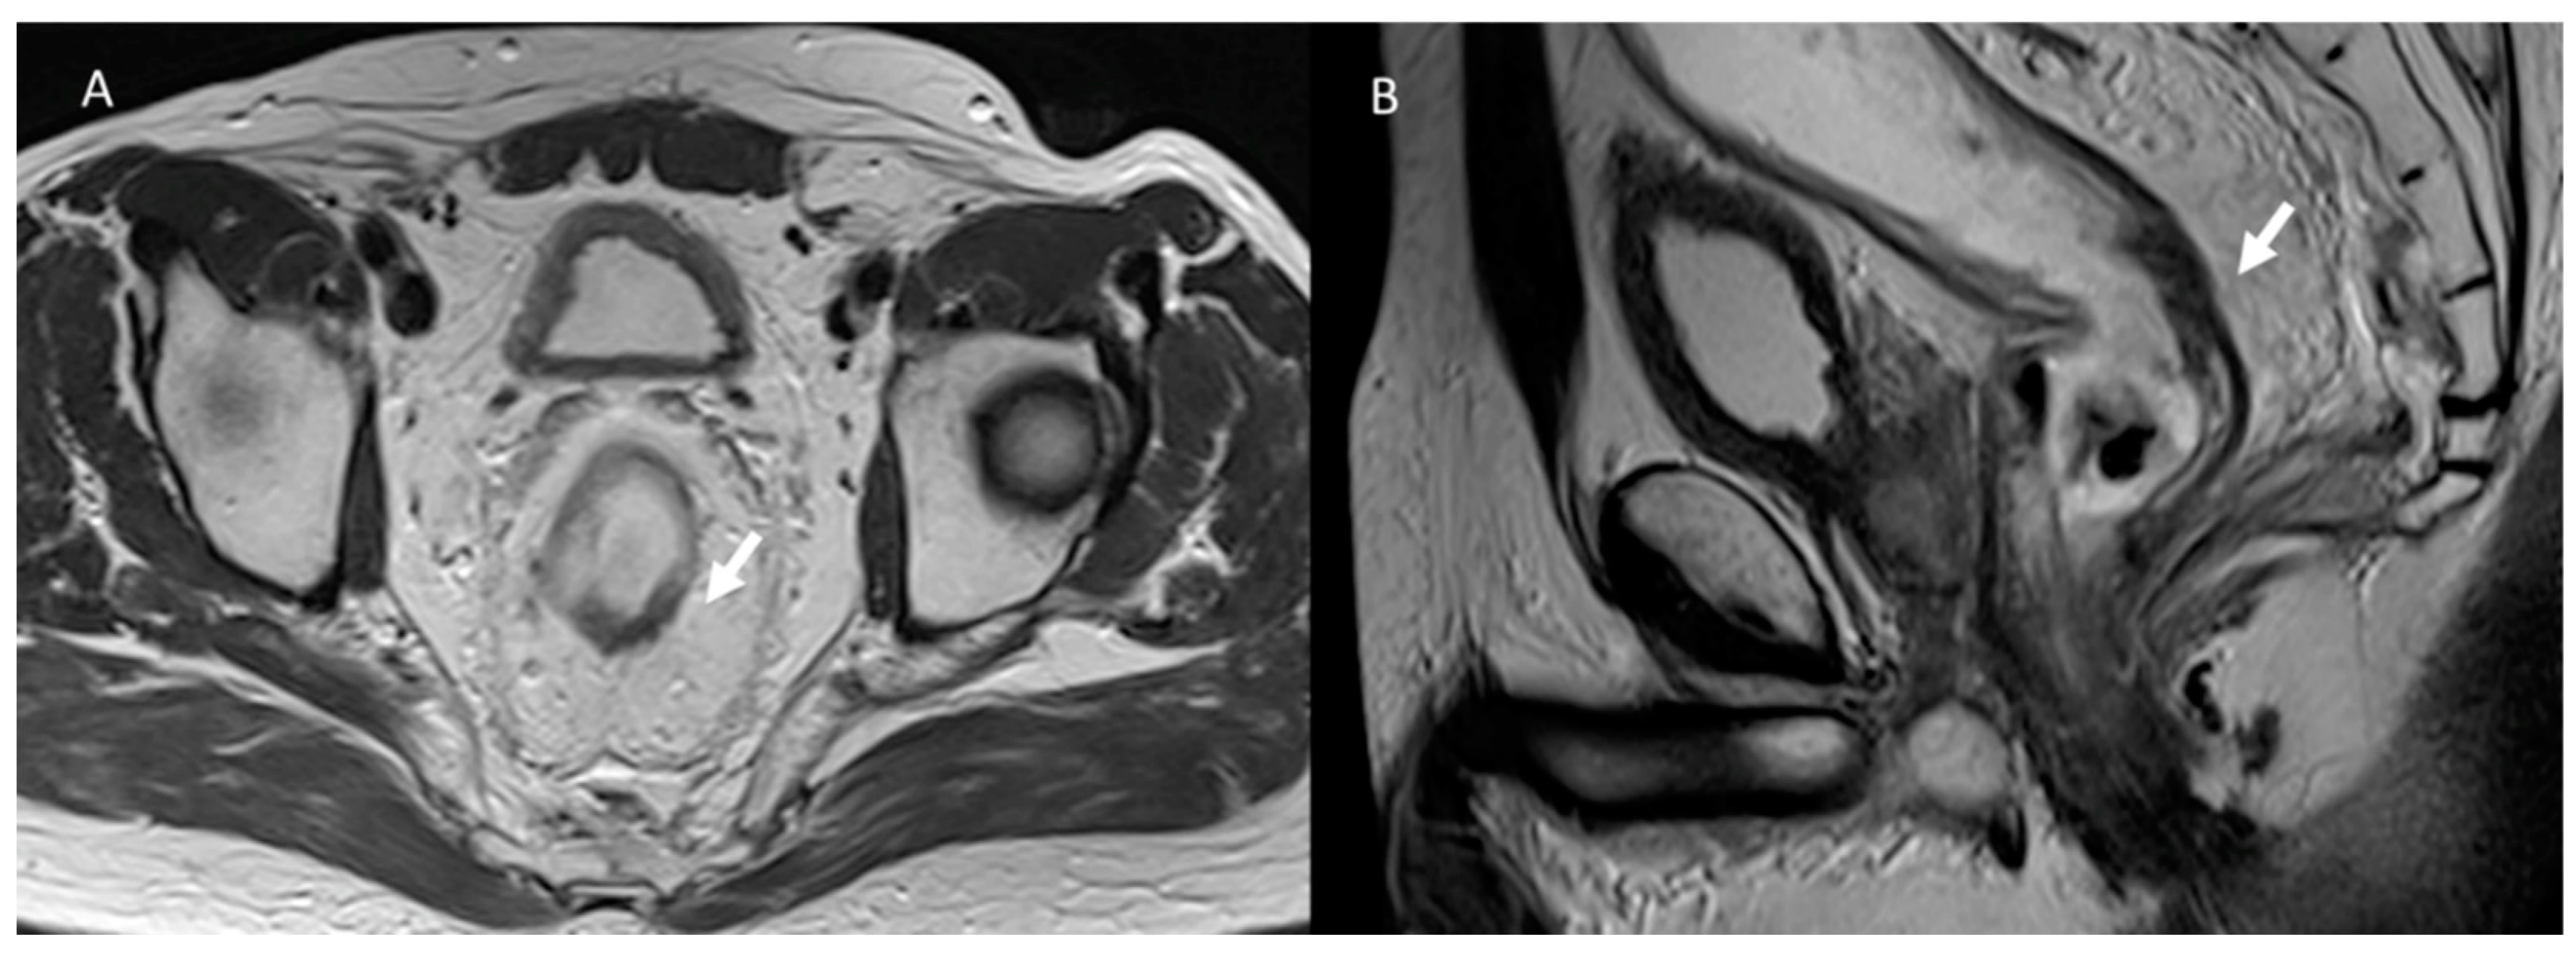

3.2. Fistula

3.3. Bleeding

3.4. Urological Injury

3.5. Wound Infections

3.6. Hernia

3.7. Local Recurrence